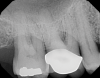

Fig 5. Pretreatment occlusal views: maxilla (Fig 5) and mandible (Fig 6).

Figure 5

Fig 6. Pretreatment occlusal views: maxilla (Fig 5) and mandible (Fig 6).

Figure 6

Periodontal examination revealed generalized BOP and PDs up to 9 mm in the maxillary and mandibular molars with multiple furcations in each molar (Figure 2 through Figure 7). He presented with class I mobility in many posterior teeth and class II mobility in teeth Nos. 3 and 9 (maxillary right first molar and maxillary left central incisor, respectively). The periodontist decided to score tooth No. 3 for the PRS, as this was the most periodontally involved molar that was planned to be treated and maintained (Figure 2 and Figure 8). This tooth (maxillary right first molar = score 1) presented with probing depths of 7 mm (score 1); three total furcation invasions (score 3) (mesial [degree II furcation], buccal [degree I furcation], and distal [degree II furcation]); and a class II mobility (score 2). The total PRS for tooth No. 3 was 8, representing a "guarded" prognosis. Based on this score, the likelihood of not losing any teeth to periodontal disease for 15 years was 81%, and for 30 years the likelihood was just 56% (Figure 9).7